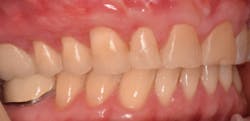

This new biological approach involving blood derivatives A-PRF and I-PRF combined with precision minimally invasive surgery for root coverage demonstrates faster healing without the need of a donor site. The morbidity of GDT is decreased and patient case acceptance is higher compared with traditional grafts. Before-and-after pictures are shown below (figures 15–22).